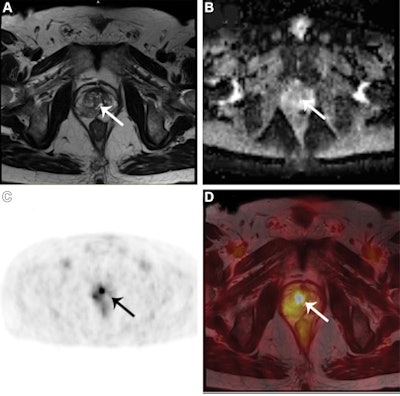

(A) Axial T2-weighted (B) axial apparent diffusion coefficient map, (C) Ga-68 PSMA PET, and (D) fused T2-weighted and Ga-68 PSMA PET/MRI scans in a 64-year-old man with a PI-RADS grade 3 lesion (arrows in A-D) in the right transition zone at multiparametric MRI. Maximum standardized uptake value (SUVmax) in A-D was 4.4. Targeted fusion biopsy diagnosed an International Society of Urological Pathology grade 2 prostate cancer. Image courtesy of Radiology.

Multiparametric MRI scores of at least 3 on the Prostate Imaging and Data System (PI-RADS) system were considered abnormal findings, while Ga-68 PSMA PET scans that showed maximum standardized uptake values (SUVmax) of at least 2.5 g/mL were considered positive findings.

The researchers found that specificity was 76% for Ga-68 PSMA PET/MRI compared with 49% for multiparametric MRI for detecting clinically significant prostate cancer. Sensitivity was similar between the two approaches. For PI-RADS 3 lesions, specificity was also higher for Ga-68 PSMA PET/MRI than for multiparametric MRI at 86% versus 59%.